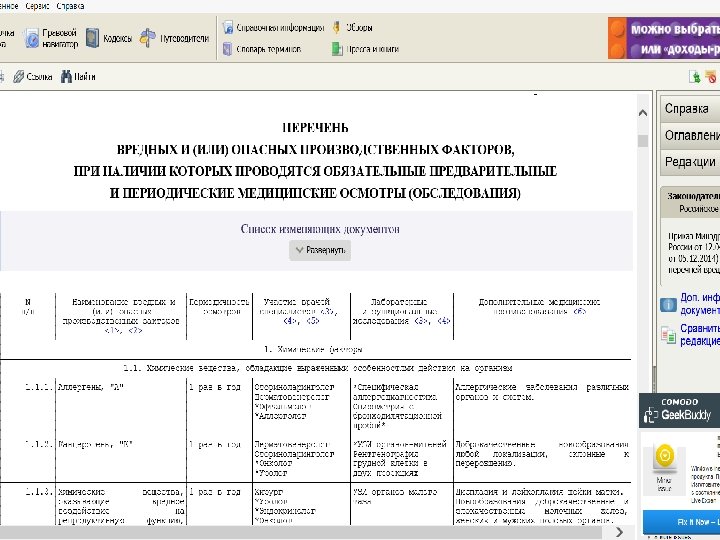

Приказ Минздравсоцразвития России от 12. 04. 2011 г. № 302 н «Об утверждении перечней вредных и (или) опасных производственных факторов и работ, при выполнении которых проводятся обязательные предварительные и периодические медицинские осмотры (обследования), и порядка проведения обязательных предварительных и периодических медицинских осмотров (обследований) работников, занятых на тяжелых работах и на работах с вредными и (или) опасными условиями труда» Утвердить: перечень вредных и (или) опасных производственных факторов, при наличии которых проводятся обязательные предварительные и периодические медицинские осмотры (обследования), согласно приложению N 1; перечень работ, при выполнении которых проводятся обязательные предварительные и периодические медицинские осмотры (обследования) работников, согласно приложению N 2; порядок проведения обязательных предварительных (при поступлении на работу) и периодических медицинских осмотров (обследований) работников, занятых на тяжелых работах и на работах с вредными и (или) опасными условиями труда, согласно приложению N 3.

Приказ Минздравсоцразвития России от 12. 04. 2011 г. № 302 н «Об утверждении перечней вредных и (или) опасных производственных факторов и работ, при выполнении которых проводятся обязательные предварительные и периодические медицинские осмотры (обследования), и порядка проведения обязательных предварительных и периодических медицинских осмотров (обследований) работников, занятых на тяжелых работах и на работах с вредными и (или) опасными условиями труда» Утвердить: перечень вредных и (или) опасных производственных факторов, при наличии которых проводятся обязательные предварительные и периодические медицинские осмотры (обследования), согласно приложению N 1; перечень работ, при выполнении которых проводятся обязательные предварительные и периодические медицинские осмотры (обследования) работников, согласно приложению N 2; порядок проведения обязательных предварительных (при поступлении на работу) и периодических медицинских осмотров (обследований) работников, занятых на тяжелых работах и на работах с вредными и (или) опасными условиями труда, согласно приложению N 3.